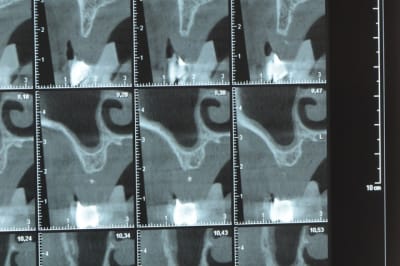

Une petite étude de ton cas D57

Sous réserves bien sur de voir l’animal en vrai

Les zones exploitables radiologiquement parlant:

Coupes implant

2,3 40100

4,96 35130 avec sinus lift mais difficile

5,25 35150

6,02 35130

6,78 35115 après réduction de hauteur de crête

7,26 35115 après réduction de hauteur de crête

8,51 35150

10,43 40115 ou 50115

11,10 40115

Ce qui nous fait 9 implants possible évidement avec un comblement de sinus on augmenterait encore les zones implantable mais ce n’est pas le but recherché, avec 8 (4+4) il doit être possible de faire une belle barre support de complet